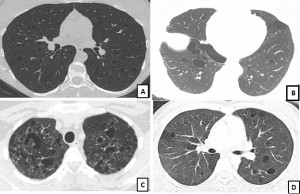

Key to Images/Quiz: A: LAM: CT chest showing round, uniform, thin-walled cysts present diffusely with a normal appearing intervening lung parenchyma B: BHD: CT chest showing oval, lentiform cysts with thin walls, predominantly in the basilar regions, and abutting the pleural surface C: PLCH: CT chest showing multiple bizarre shaped cysts of varying sizes, present in an upper lobe predominant distribution D: Sjogren’s syndrome related cystic lung disease: CT chest showing multiple round-oval cysts in a random distribution. Note, that some of these cysts have an eccentric vessel, and some cysts also seem to have internal structures within them.